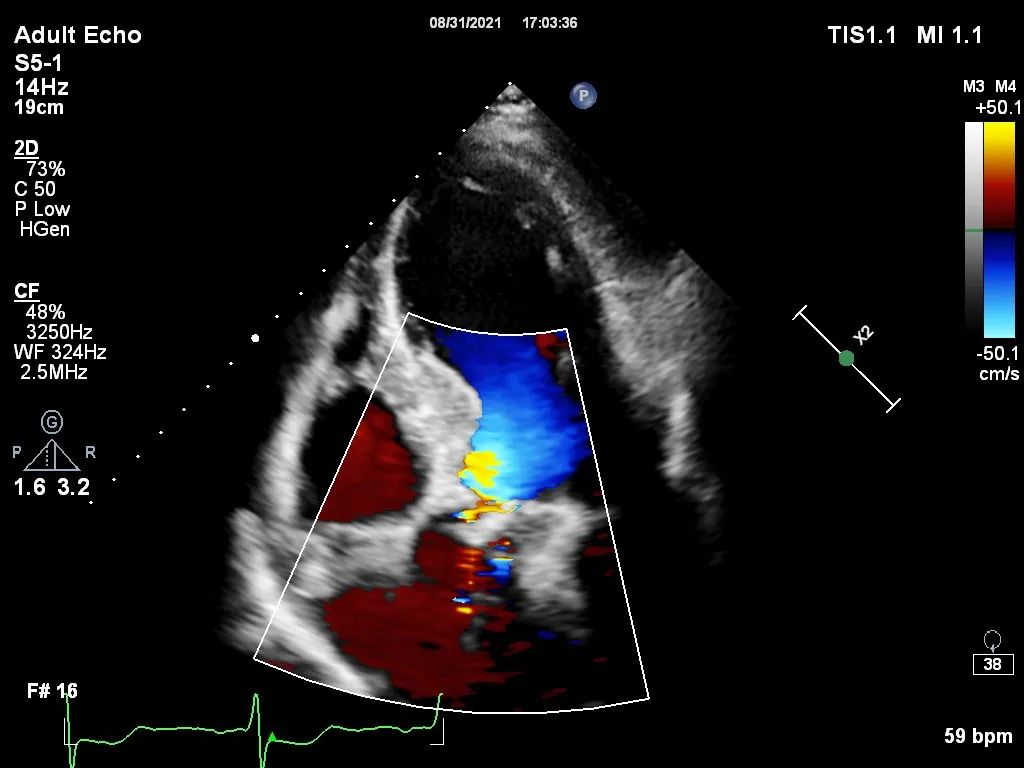

心脏彩超

主动脉瓣评估:左心扩大,主动脉瓣狭窄重度伴轻度反流

瓣膜形态,极微量周漏

经过2个小时紧张有序的操作,手术取得圆满成功。术后即刻显示,瓣膜释放完毕后,患者的血流动力学状态明显好转,主动脉瓣前向血流速度降至1.6m/s,且瓣周漏近乎为零,达到了预期的治疗效果,患者苏醒后顺利从CCU转至普通病房。